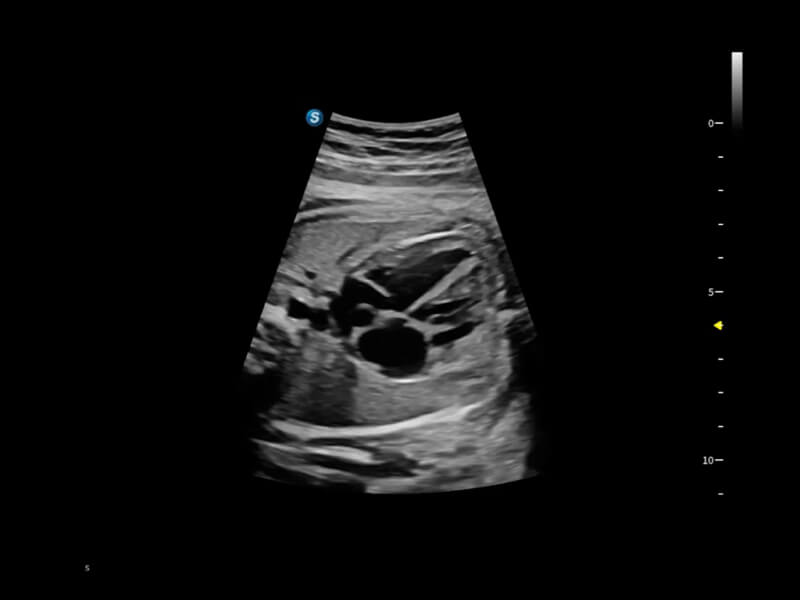

Image quality always lies at the core of definitive clinical outcomes. The P80 Elite introduces evolutional transducers with excellent 2D image clarity and color sensitivity for more confident assessment in anatomy and pathology.

Premium Transducer Solution

P80 Elite provides a series of advanced specialized transducers to empower ultrasound professionals for more confident and efficient assessment of anatomy to fullfill women’s healthcare needs.